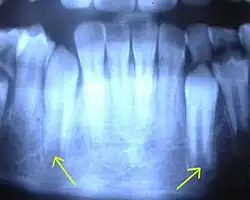

Unter einer Apexifikation (Latein: apex ‚Spitze‘, Suffix -ficatio ‚das Herstellen‘) versteht man ein Verfahren in der Zahnmedizin, mit dem ein apikal (an der Wurzelspitze) offener Wurzelkanal vor der eigentlichen Wurzelkanalfüllung verschlossen wird. Die Apexifikation wird vor allem bei devitalen (abgestorbenen) jugendlichen Zähnen mit noch nicht abgeschlossenem Wurzelwachstum angewandt. Mit der Apexifikation wird eine natürliche oder künstliche Hartsubstanzbarriere an der Wurzelspitze erzeugt, je nach verwendetem Material.[1]

Zähne mit abgeschlossenem Wurzelwachstum weisen am Apex (an der Wurzelspitze) eine apikale Konstriktion (verengte Stelle an der Wurzelspitze) auf, an welcher der Wurzelkanal durch Hartsubstanzanlagerung den schmalsten Querschnitt aufweist. Ohne diese Einengung besteht bei der Wurzelkanalfüllung eines Zahns die Gefahr, den Kanal zu überfüllen, wodurch Material ins umliegende apikale Gewebe, den Knochen und – bei Behandlung im Oberkiefer – auch in die Kieferhöhle gelangen könnte.

Mit Calciumhydroxid wird eine natürliche Hartsubstanzbildung an der Wurzelspitze über 6 bis 18 Monate angeregt. Calciumhydroxid stimuliert über seinen stark basischen pH-Wert reaktiv langsam die Neubildung von Zahnhartsubstanz. Nach einer röntgenologisch nachweisbarer Apexifikation kann die abschließende Wurzelkanalfüllung relativ gefahrlos hinsichtlich einer unerwünschten Überfüllung durchgeführt werden.[2]